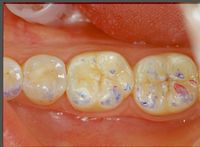

File:Clicker end4.jpg|'''Figure 9d:''' Peculiarities of neurognathological parameters. Occlusal view of the right mediotrusive detail. (work done in 1992)

In figure 9c and 9d, we can see not only the well balanced centric contacts but above all the mediotrusive excursions. A few more words should be spent on this subject. Benedikt Sagl et al.<ref>Sagl B, Schmid-Schwap M, Piehslinger E, Rausch-Fan X, Stavness I. The effect of tooth cusp morphology and grinding direction on TMJ loading during bruxism. Front Physiol. 2022 Sep 15;13:964930. doi: 10.3389/fphys.2022.964930. eCollection 2022.PMID: 36187792 </ref> state, in their study in which the contribution of tooth inclination, medio-otrusive and laterotrusive excursion and von Mises stresses on the articular disc was analysed, that mediotrusive bruxing generates higher loads than laterotrusive simulations. In this sense it is not clear whether the mediotrusive contacts are a protective or a pejorative element in the generation of temporomandibular joint disorders. So much so that an article by Walton TR and Layton DM<ref>Walton TR, Layton DM. Mediotrusive Occlusal Contacts: Best Evidence Consensus Statement. J Prosthodont. 2021 Apr;30(S1):43-51. doi: 10.1111/jopr.13328.PMID: 33783093</ref> increases the confusion as they first state that the presence of TM interference in patient populations is large and varies from 0% to 77% and then conclude that TM interference should be avoided in any occlusal treatment regimen to minimize pulpal, periodontal, structural and mechanical complications or exacerbation of temporomandibular disorders (TMD). The confusion increases when he concludes that natural molar MT interferences should only be eliminated if signs and symptoms of TMD are present. The question that arises is the following

In figure 9c and 9d, we can see not only the well balanced centric contacts but above all the mediotrusive excursions. A few more words should be spent on this subject. Benedikt Sagl et al.[19] state, in their study in which the contribution of tooth inclination, medio-otrusive and laterotrusive excursion and von Mises stresses on the articular disc was analysed, that mediotrusive bruxing generates higher loads than laterotrusive simulations. In this sense it is not clear whether the mediotrusive contacts are a protective or a pejorative element in the generation of temporomandibular joint disorders. So much so that an article by Walton TR and Layton DM[20] increases the confusion as they first state that the presence of TM interference in patient populations is large and varies from 0% to 77% and then conclude that TM interference should be avoided in any occlusal treatment regimen to minimize pulpal, periodontal, structural and mechanical complications or exacerbation of temporomandibular disorders (TMD). The confusion increases when he concludes that natural molar MT interferences should only be eliminated if signs and symptoms of TMD are present. The question that arises is the following

In figure 9c and 9d the mediotrusive path highlighted with the articulation paper was constructed by calculating the angle determined by the unilateral Root-MEPs which displaces the mandible by about 1/2mm on each side. By programming the Denar joint (figure 10) it was possible to construct an excursion with different angles between the TMJ, molar and canine. This procedure generates a natural path in which the canine guides together with the mediotrusion to protect the TMJ from the masticatory load that exists beyond bruxism.